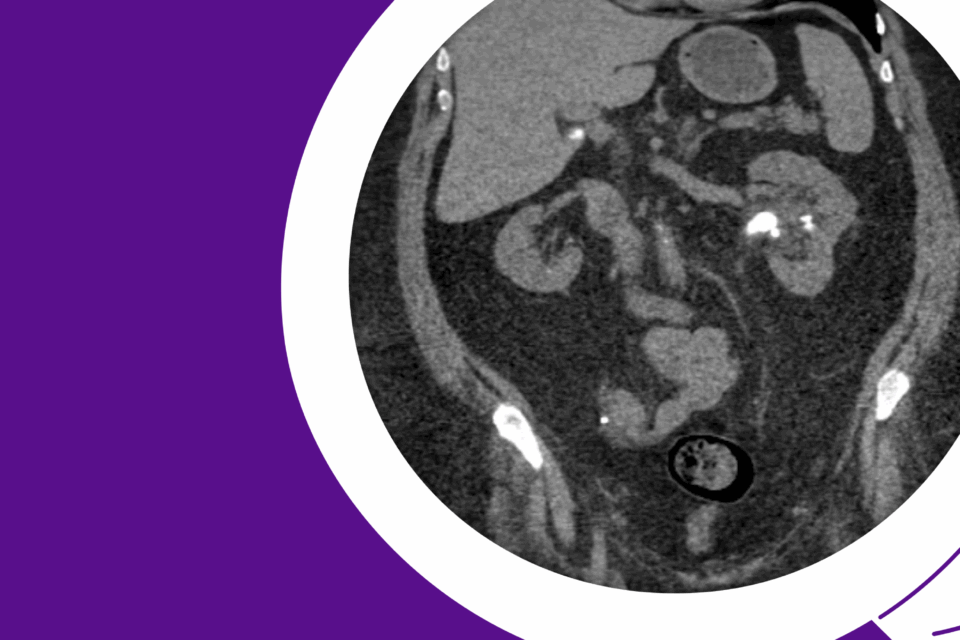

Dr. Wei Phin Tan managed Grade Group 5 disease (Gleason 4+5) while preserving urethral length and continence and achieving undetectable PSA at three months.